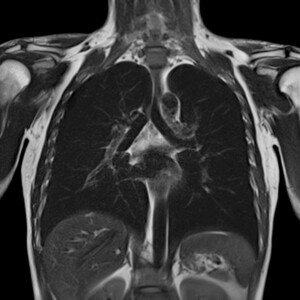

La polyclinique ibn rochd a connu une grande évolution lors des dernières années, forts de notre longue expérience de plus de 40 ans dans le domaine médical au Maroc, on propose à nos chers patients des solutions adéquates et parfaitement mises en place en vue de subvenir à leurs besoins en matière d’incommodités au niveau de leur santé individuelle. Parmi les techniques qu’on utilise chaque jour au sein de notre polyclinique ultra moderne se trouve celle de la chirurgie thoracoscopique en compagnie de vidéo assistée, elle permet à nos spécialistes éminents de relever les données importantes concernant les aspects de l’opération chirurgicale même une fois au cœur du bloc opératoire, les instruments usés sont soigneusement élus en détails et on explore les possibilités qui sont mises sur table étape par étape dans le seul but de vous assurer une approche personnalisée et en toute sécurité pour votre santé qui nous importe tant !